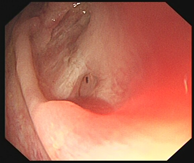

考虑直肠存在瘘口,遂再次行肠镜,肠镜检查除了发现回肠末端及结直肠多发溃疡,最重要的是发现直肠的确存在针尖样大小的瘘口(图3)。

图3  直肠内瘘口扩张前